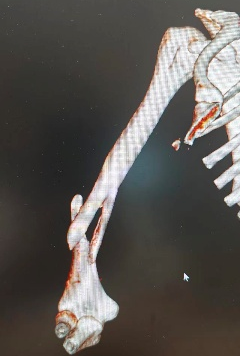

10月4日,59岁张先生不慎被他人电瓶车撞伤致左踝、左小腿疼痛,来院就诊后,王建伟医师团队为患者实行“左胫骨骨折切开复位内固定术”